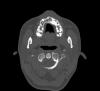

persona Опубликовано 12 октября, 2008 Автор Поделиться Опубликовано 12 октября, 2008 (изменено) Кроме того, проходил КТ. Выкладываю несколько срезов в области клыка. Изменено 12 октября, 2008 пользователем persona Ссылка на комментарий